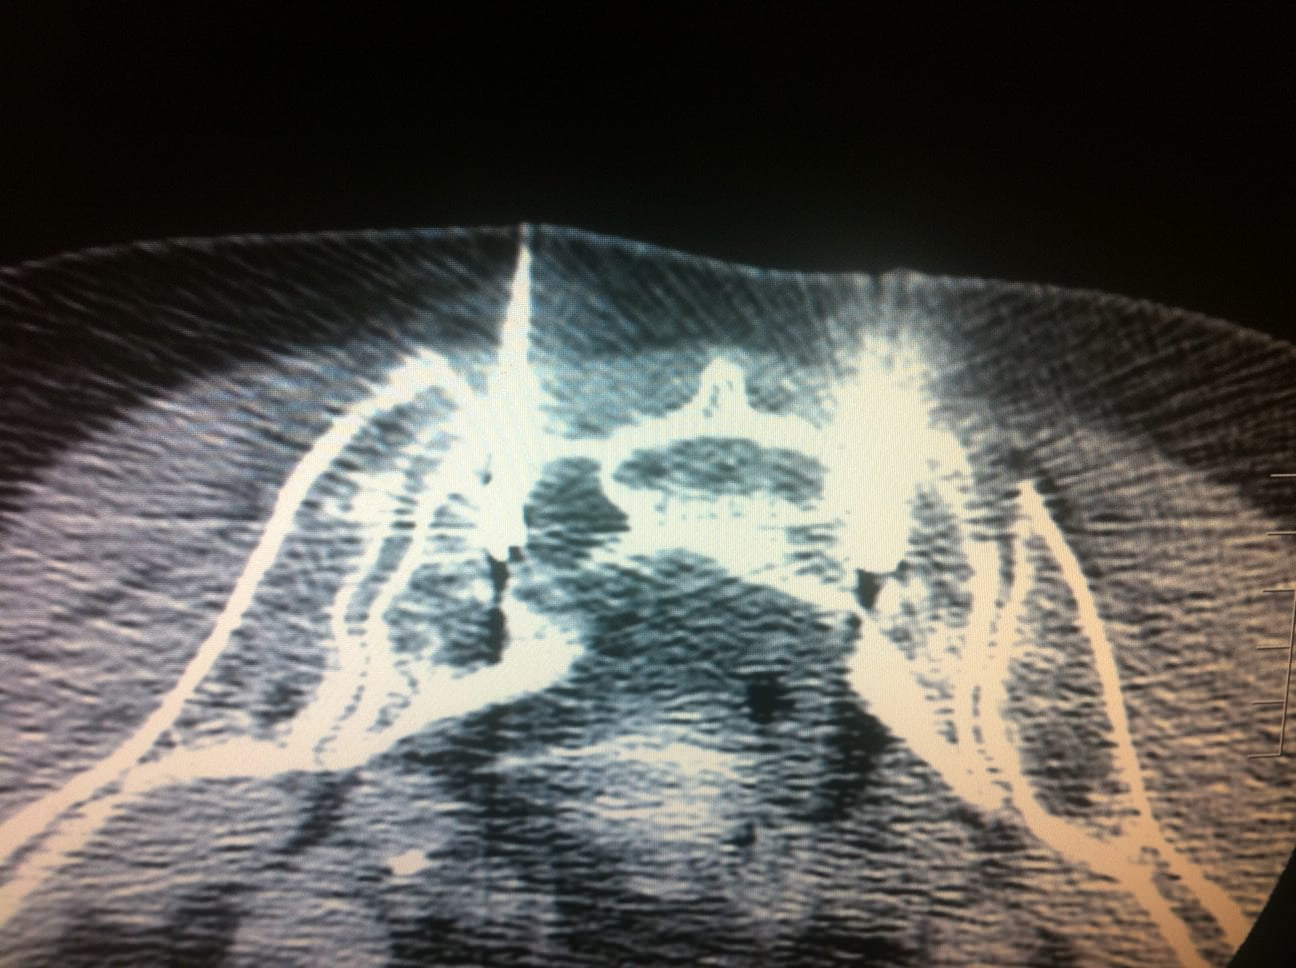

Sacral fracture Image Fracture Du Sacrum Et Sport La consolidation d’une fracture du sacrum est un processus qui nécessite du temps, de la patience et des soins appropriés. Fractures, or breaks, in this bone are often very painful injuries that can require weeks or months of bed rest to heal. Un orthopédiste explique s’il est bon de refaire du sport après une pause forcée due à une fracture. Fracture Du Sacrum Et Sport.

Fracture de contrainte du sacrum Figure 2B Fracture Du Sacrum Et Sport Une fracture du sacrum peut survenir en raison d’un accident de la route, d’une chute, d’un sport de contact ou d’une mauvaise. Un orthopédiste explique s’il est bon de refaire du sport après une pause forcée due à une fracture et comment s’y prendre. Découvrez le diagnostic, le traitement et les conséquences de la fracture du sacrum sur votre capacité. Fracture Du Sacrum Et Sport.

Fracture de contrainte du sacrum Figure 1A Fracture Du Sacrum Et Sport Vous souhaitez retourner à l’entraînement après une fracture du pied? Il convient simplement de prendre quelques précautions. La consolidation d’une fracture du sacrum est un processus qui nécessite du temps, de la patience et des soins appropriés. Il est tout à fait possible de reprendre le sport après une fracture. Une fracture du sacrum peut survenir en raison d’un accident. Fracture Du Sacrum Et Sport.

Fracture de contrainte du sacrum Figure 2A Fracture Du Sacrum Et Sport Fractures, or breaks, in this bone are often very painful injuries that can require weeks or months of bed rest to heal. Following the bed rest, your doctor is likely to prescribe exercises to help. Il convient simplement de prendre quelques précautions. Il est tout à fait possible de reprendre le sport après une fracture. Vous souhaitez retourner à l’entraînement. Fracture Du Sacrum Et Sport.